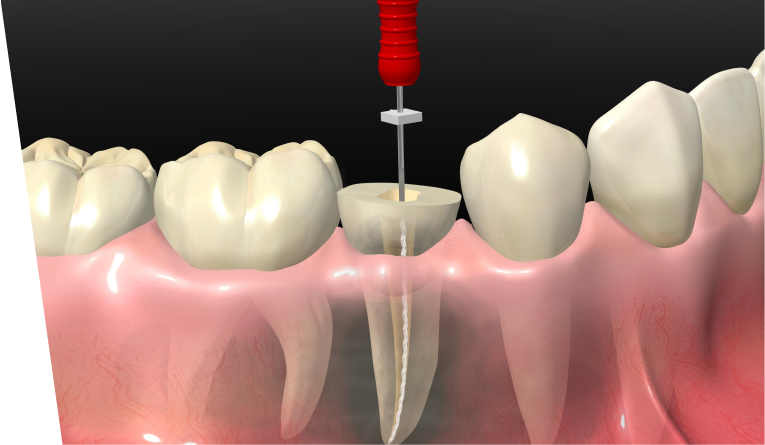

虫歯が進行して神経まで達すると、温かい物がしみたり、何もしなくても痛むことがあります。

歯の神経や感染部分を取り除く根管治療が必要となります。

マイクロスコープは、根管内を拡大し明るい状態で確認できます。肉眼では見えにくい部分も把握しやすく、感染した歯髄の除去を精密に行うことができます。

根管治療後の再発率は約30〜70%といわれています。根管の先端は直径0.25mm程度と非常に細く、精密な処置には専用の機器や設備が欠かせません。

たかた歯科医院では、精度の高い根管治療を行うために、以下のような取り組みを行っています。